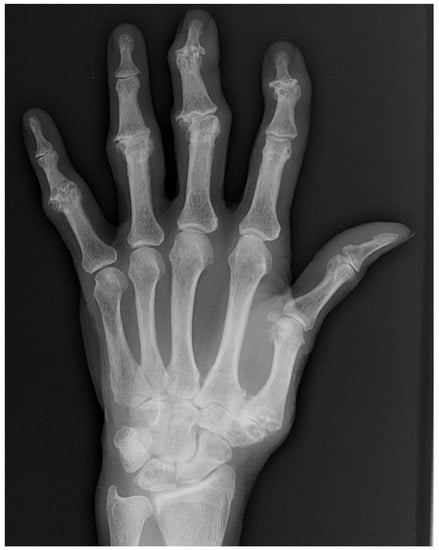

4. Rheumatoid Arthritis

9. Systemic Lupus Erythematous (SLE)